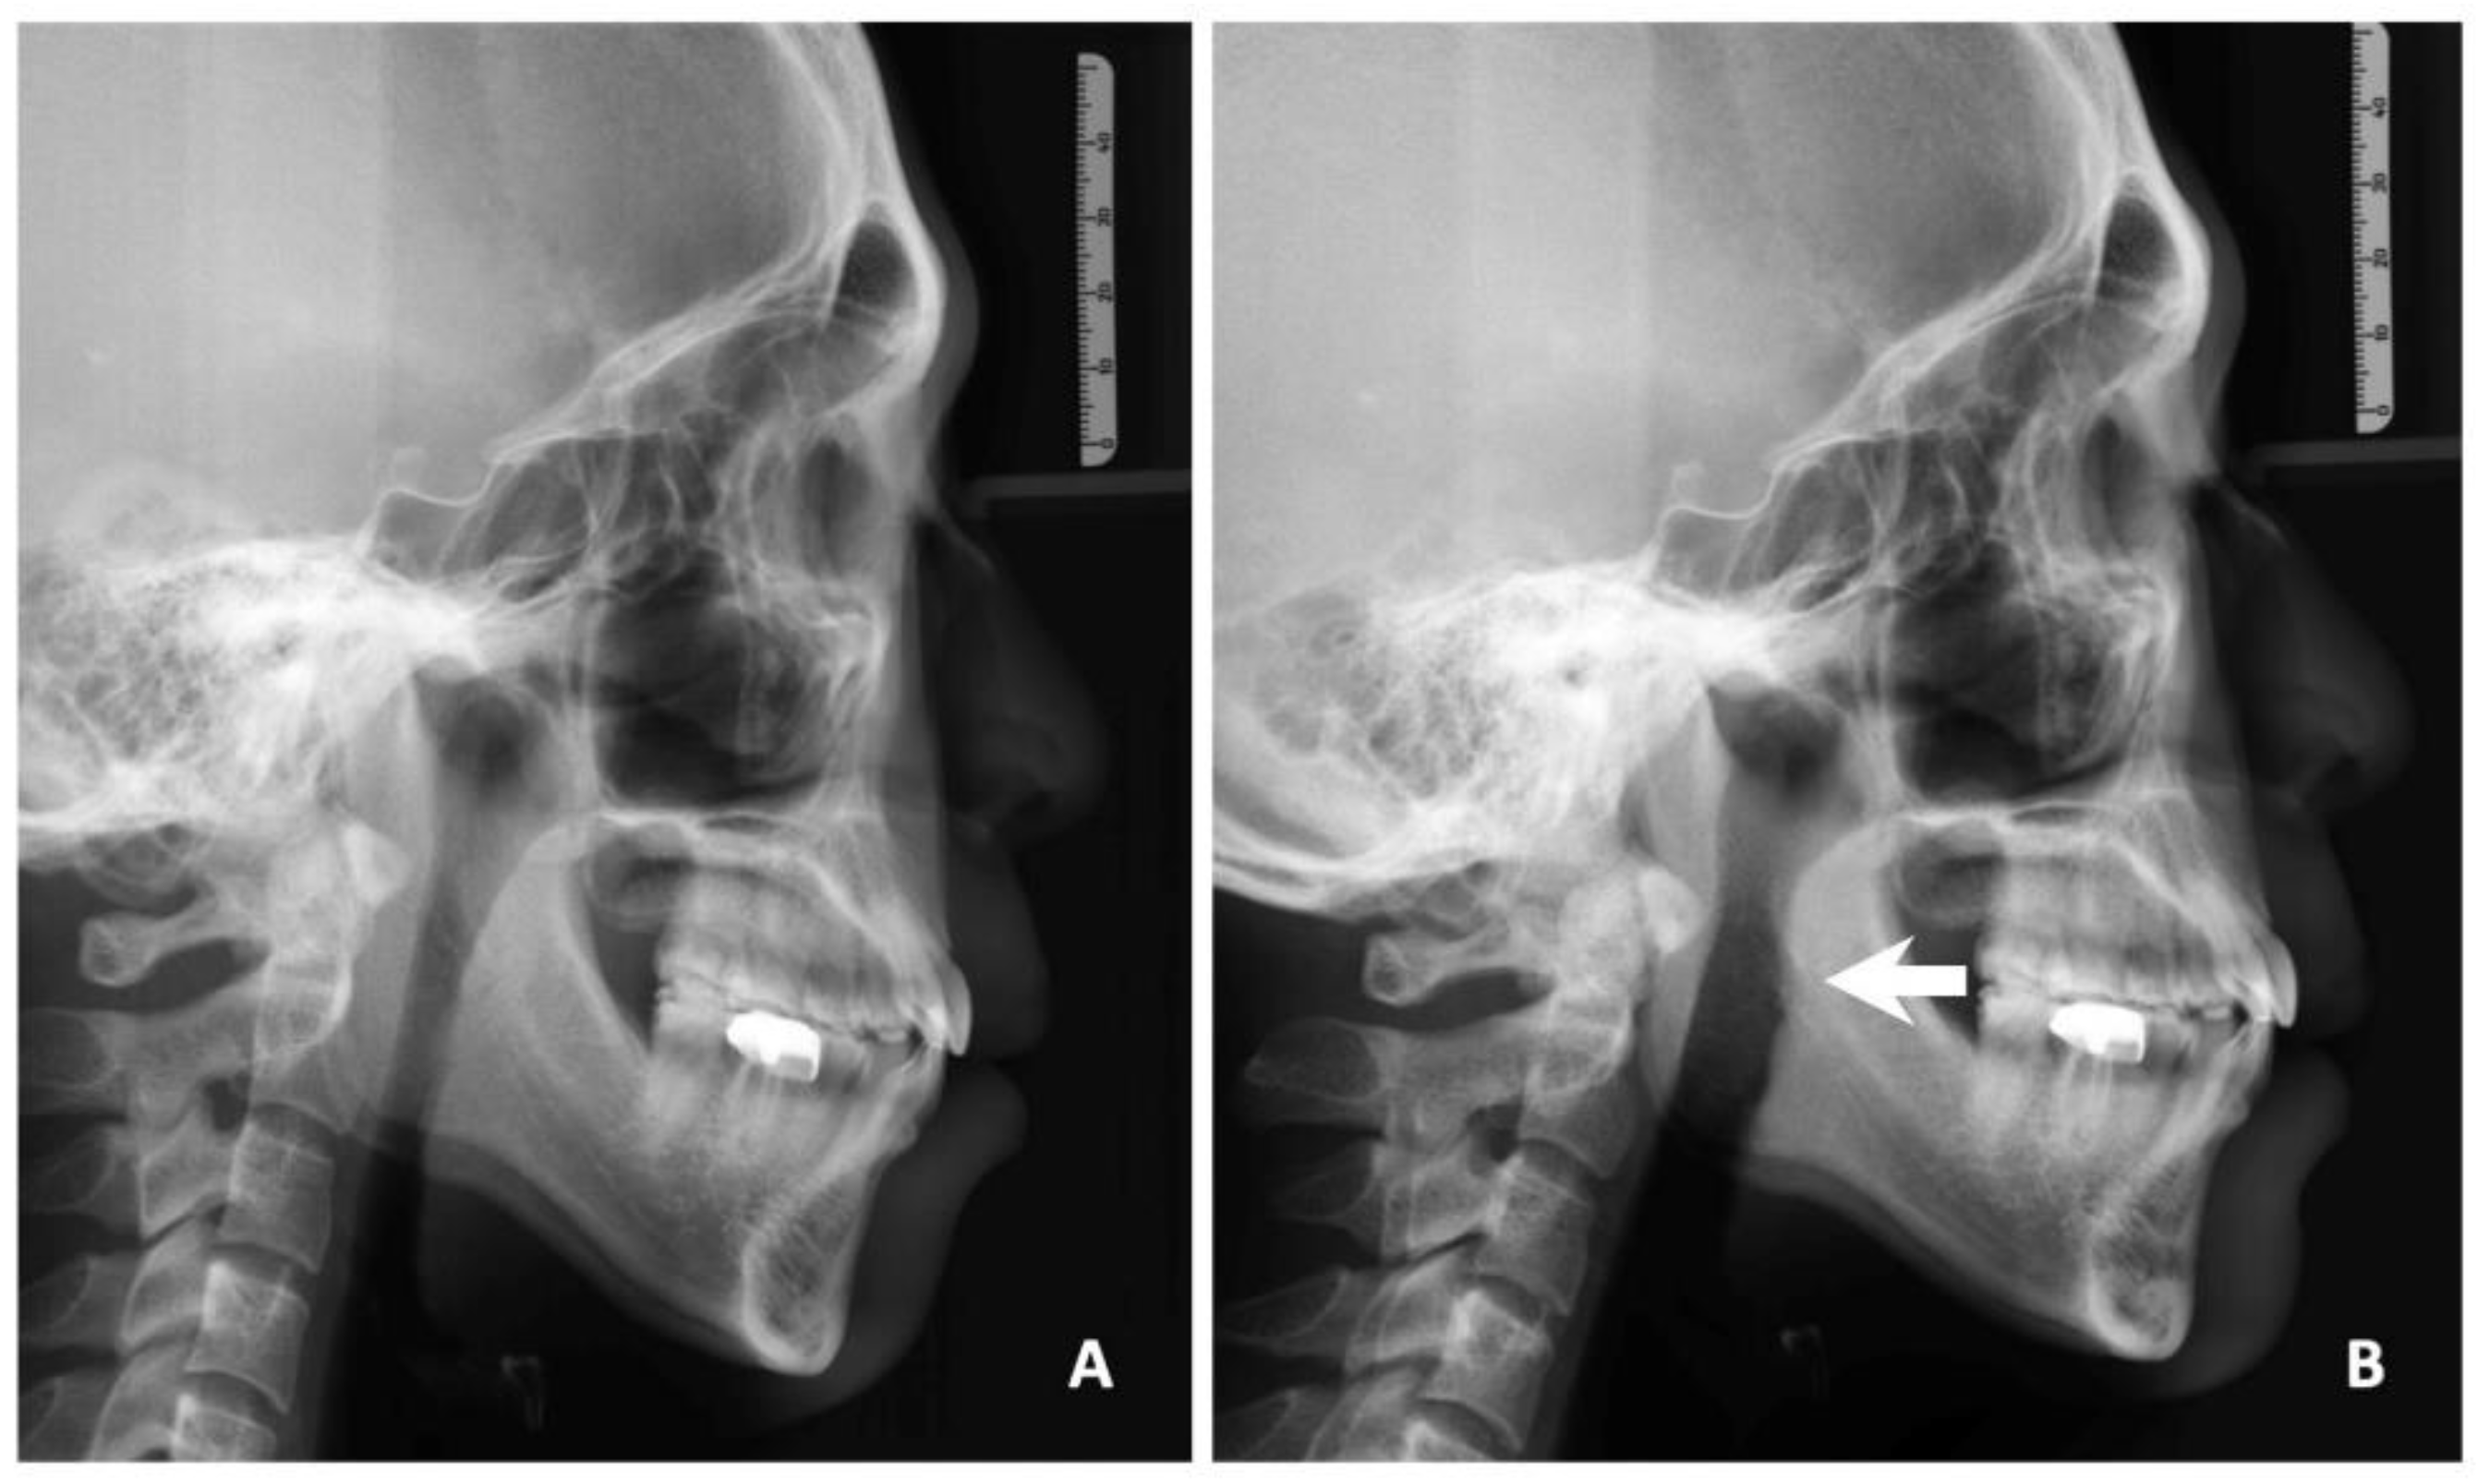

2.3. Surgical Technique of TOTS